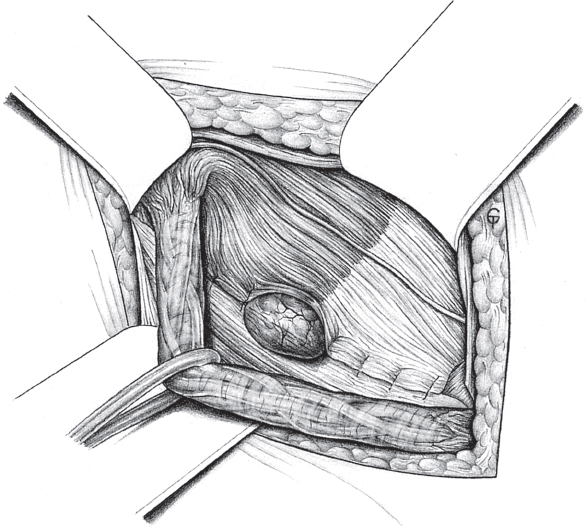

If a femoral hernia is found in addition during open surgery, TIPP repair can be used without slitting the mesh laterally (see section

2.3.2) or the Lichtenstein repair can be modified by fixing the medial part of the mesh to the Cooper ligament rather than to the inguinal ligament (

Fig. 3.3). Suture of the mesh starts as usual over the pubic bone, without picking up the periosteum. From there, the suture passes from medial to lateral between the Cooper ligament and the inferior border of the mesh as far as the femoral vein. The suture ascends here to the base of the inguinal ligament and continues beyond the deep inguinal ring, as in men. The mesh is fixed cranially by the usual method of tying it loosely to the internal oblique muscle. At the deep inguinal ring, the proximal stump of the round ligament can be fixed to the mesh.

Fig. 3.3 Lichtenstein repair of a combined hernia with a femoral hernial orifice. Schematic cross-section of mesh position medial to the femoral vein.